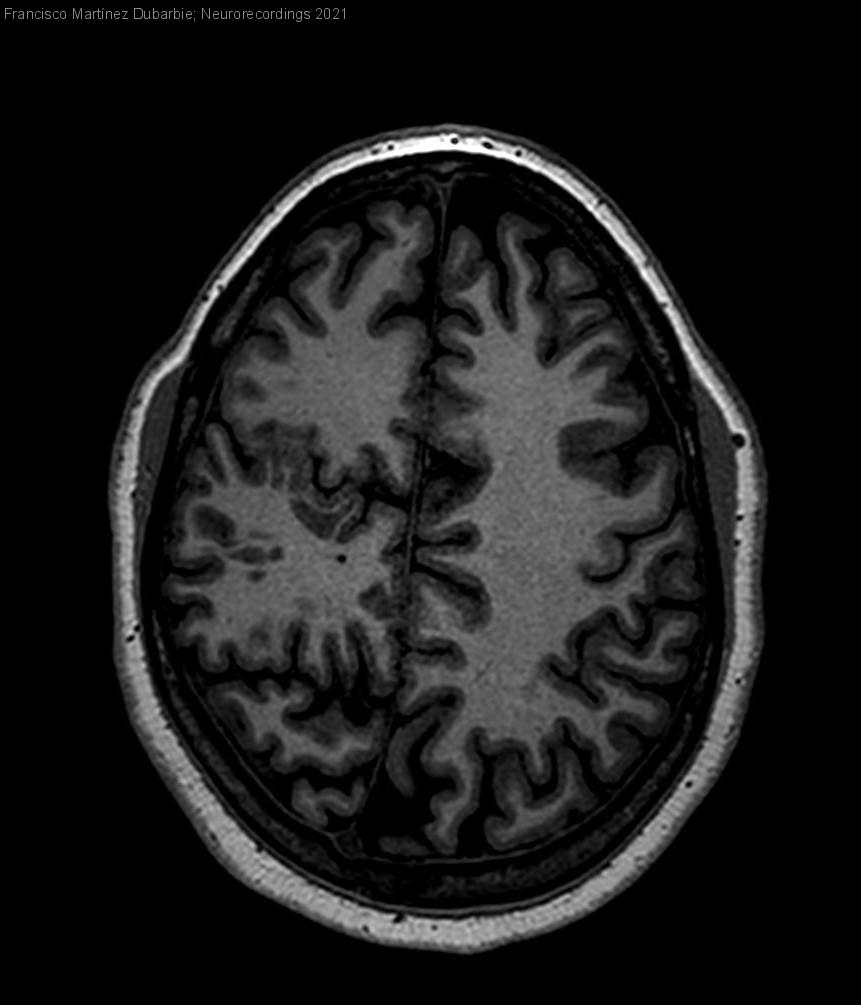

Epilepsia focal en paciente con malformación cerebral compleja.

Mujer | 35 años

Diagnóstico final: Crisis focal frontal. Polimicrogiria.